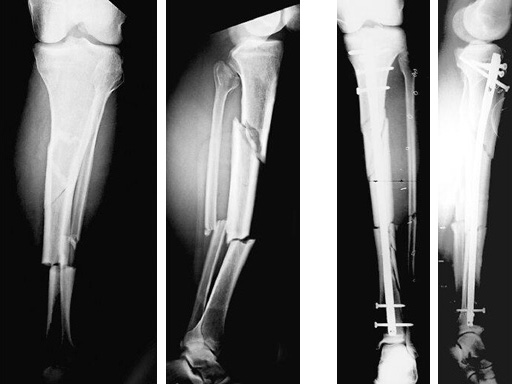

Type III open distal tibial fracture with beginning compartment syndrom following a traffic accident.

47-year-old man with closed 42-C3 fracture following a sports accident treated with ETNS.